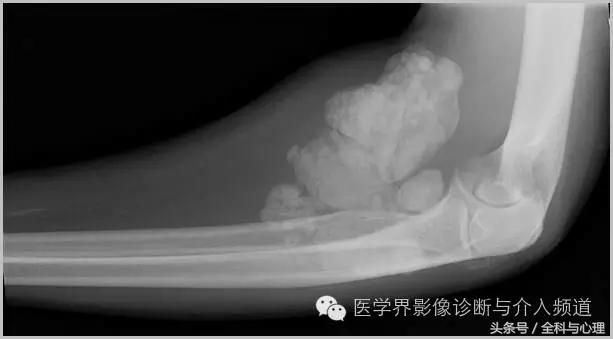

一、肿瘤样钙质沉着症

累及多个关节,范围较大,表现为多房囊状的高密度影。

肿瘤样钙质沉着症